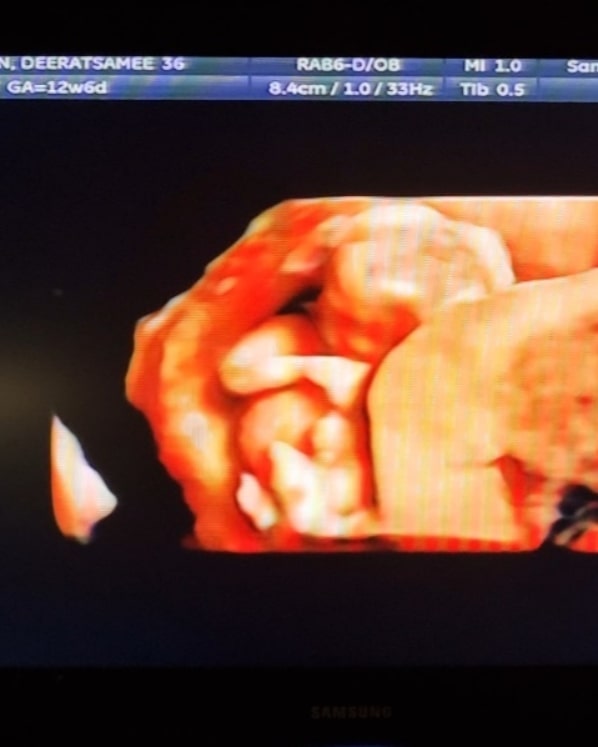

โดยล่าสุด (24 ธันวาคม 2564) สาว แนนนี่ เกิร์ลลี่ เบอร์รี่ ได้โพสต์อินสตาแกรมแจ้งข่าวดีในคืนวันคริสต์มาสอีฟ เผยของขวัญที่ดีที่สุดของปีนี้ นั่นก็คือลูกน้อยที่กำลังจะเกิดมาของคู่ว่าที่บ่าวสาว ซึ่งตอนนี้พ่วงตำแหน่งว่าที่คุณพ่อคุณแม่เป็นที่เรียบร้อยแล้ว

โดยนอกจากเผยภาพอัลตราซาวน์ของเบบี๋ในครรภ์ แนนนี่ยังเผยว่า "พ้นช่วงลุ้นระทึกมาแล้ว เข้าสู่ไตรมาส 2 แล้วประกาศได้